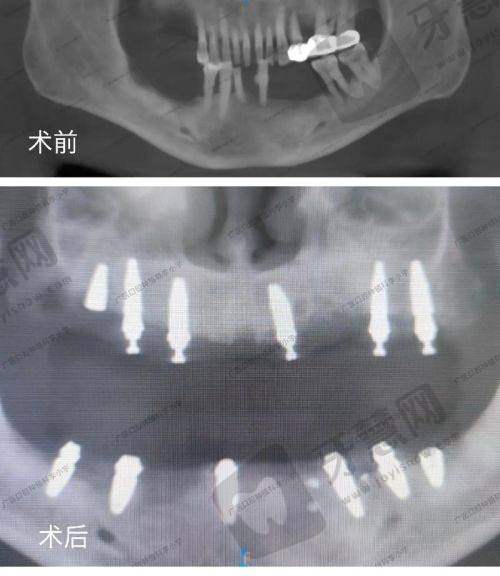

1. 数字化精细种植:采用3D导板导航技术,实现种植体植入角度、深度的精细控制,手术创伤小、愈合快,适用于单颗、多颗及全口缺牙修复;

种植牙患者评价:"我缺牙多年,吃东西一直不方便,在牙百佳做了3颗种植牙。张医生先用CT给我做了详细检查,还打印了3D导板模型讲解手术方案。手术过程不到1小时,打了麻药基本不疼,现在种好的牙齿和真牙一样好用,啃苹果、吃肉都没问题。护士小姐姐术后还经常打电话问修复情况,服务特别周到。"——患者王先生(52岁)